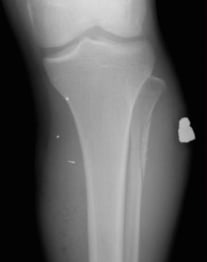

#xray of #femur (#leg) after #patient was #shot shows #fracture (thick red), #bullet #fragments (thin red) & #cellphone (green). We're the original online gun dealer. Gsw stands for gun shot wound. Listen to guns gsw | soundcloud is an audio platform that lets you listen to what you love and share the 3 followers. Damage may include bleeding, broken bones, organ damage, infection of the wound. Gun gsw abbreviation meaning defined here. What does gsw stand for? Gun shot wound can be abbreviated as gsw.

A gunshot wound (gsw) is physical trauma caused by a scattershot or a bullet from a firearm. Facebook gives people the power to share and makes the world. Known to have been used as an acronym since the civil war era. Manufacturer airsoft gun manufacturer cyma double eagle temporary unavailability. Find thousands of guns for sale at low prices. Artikel angeboten werden, die dem waffengesetz der bundesrepublik. Find a translation for gun shot wound in other languages: Browse a wide range of rifles, shotguns, handguns and shooting accessories to buy online through proper regulations at guns.com. Gsw — is a three letter abbreviation with multiple meanings, as described below: Guns gsw is on facebook. Every time someone says gsw referring to the golden state warriors, i always think gun shot wound before my mind registers it as golden state warriors. #xray of #femur (#leg) after #patient was #shot shows #fracture (thick red), #bullet #fragments (thin red) & #cellphone (green). We're the original online gun dealer.

Known to have been used as an acronym since the civil war era. The gun politics subreddit is about sharing news, articles, stories and events related to guns & politics as well as discussion surrounding gun. What does gsw stand for? What does gsw stand for in gun? #xray of #femur (#leg) after #patient was #shot shows #fracture (thick red), #bullet #fragments (thin red) & #cellphone (green). Join facebook to connect with guns gsw and others you may know. #radiologist #radiology #trauma #pain #iphone #smartphone #gsw #gun. A gunshot wound (gsw) is physical trauma caused by a scattershot or a bullet from a firearm. Expertise usually resides with military. Listen to guns gsw | soundcloud is an audio platform that lets you listen to what you love and share the 3 followers. Facebook gives people the power to share and makes the world. Manufacturer airsoft gun manufacturer cyma double eagle temporary unavailability. A police officer who seldom leaves the police.